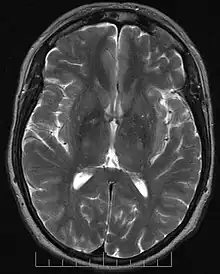

En neurosciences, la tractographie est une méthode utilisée pour mettre en évidence les voies neuronales[ref 1]. Elle utilise une technique spéciale d’IRM avec une technique particulière du tenseur de diffusion. Les résultats sont présentés sous forme d'images deux et trois dimensions.

Les séquences d’IRM utilisées en tractographie étudient la symétrie de la diffusion de l’eau dans le cerveau. Les faisceaux de fibres provoquent une diffusion asymétrique de l’eau dans un tenseur. Son axe principal est parallèle à la direction des fibres. Cette asymétrie est appelée anisotropie. Il existe un lien direct entre le nombre de fibres et le degré d’anisotropie.

La tractographie est réalisée grâce à l'imagerie du tenseur de diffusion. L'IRM de diffusion, introduite, notamment pour son potentiel en neuroimagerie par Denis Le Bihan dès 1985 [1],[2] permet d'obtenir des images de la diffusion moléculaire, notamment de l'eau. Une évolution de l'IRM de diffusion, l'imagerie du Tenseur de Diffusion [3],[4], permet de caractériser la diffusion moléculaire dans les 3 dimensions de l'espace. La diffusion libre se produit de manière homogène dans toutes les directions (mouvement brownien). On l'appelle diffusion isotropique. Si l'eau diffuse dans un milieu avec des barrières, la diffusion sera privilégiée dans certaines directions. On l'appelle diffusion anisotropique. Dans un tel cas, la mobilité des molécules à partir de leur origine de départ a une forme différente d'une sphère. La forme peut-être ellipsoïde. Cette technique est appelée technique d'imagerie du tenseur de diffusion. Les barrières peuvent être de multiples types : membranes cellulaires, axones, gaines de myéline, etc. Dans le cerveau, la principale barrière est la gaine de myéline. Des faisceaux d'axones forment une barrière empêchant une diffusion perpendiculaire et un chemin pour la diffusion parallèle le long de l'orientation des fibres. On s'attend à ce que la diffusion anisotropique soit augmentée dans les zones d'ordre axonal maximum. Dans certaines pathologies, la structure des axones est perturbée comme dans les traumatismes, les tumeurs ou les inflammations. L'anisotropie, par destruction ou désorganisation des barrières est donc augmentée. L'anisotropie est mesurée de différentes manières. L'une d'entre elles consiste à évaluer un ratio appelé anisotropie fractionnelle (AF). Une anisotropie de 0 correspond à une sphère parfaite alors qu'un ratio à 1 correspond à une diffusion linéaire idéale. Des trajets bien délimitables ont une AF plus grande que 0,20. Peu de régions ont une AF de plus de 0,80. La valeur donne une information sur la non-sphéricité de la diffusion mais ne donne pas d'information sur sa direction. Chaque anisotropie est liée à une orientation sur un axe prédominant (direction prédominate de la diffusion) Des programmes informatiques sont capables d'extraire cette information directionnelle. Cette information additionnelle est difficile à représenter sur des images en 2D en échelles de gris. Pour surmonter ce problème, un code coloré est ajouté. Des couleurs basiques informent sur l'orientation des fibres dans un système avec des coordonnées dans les 3 dimensions. On parle de plan anisotropique. Conventions de couleurs :